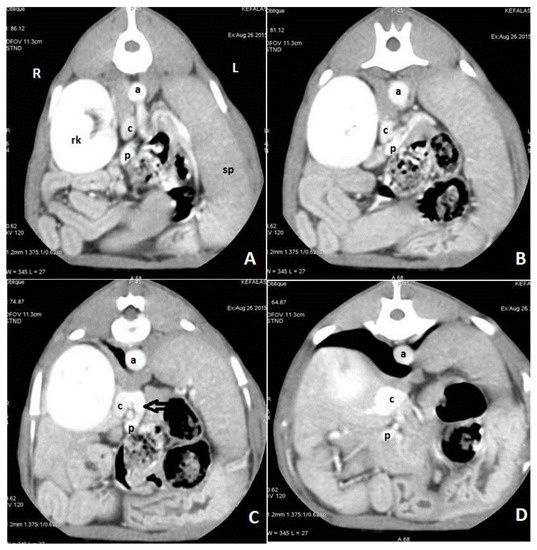

9. Diagnostic Imaging